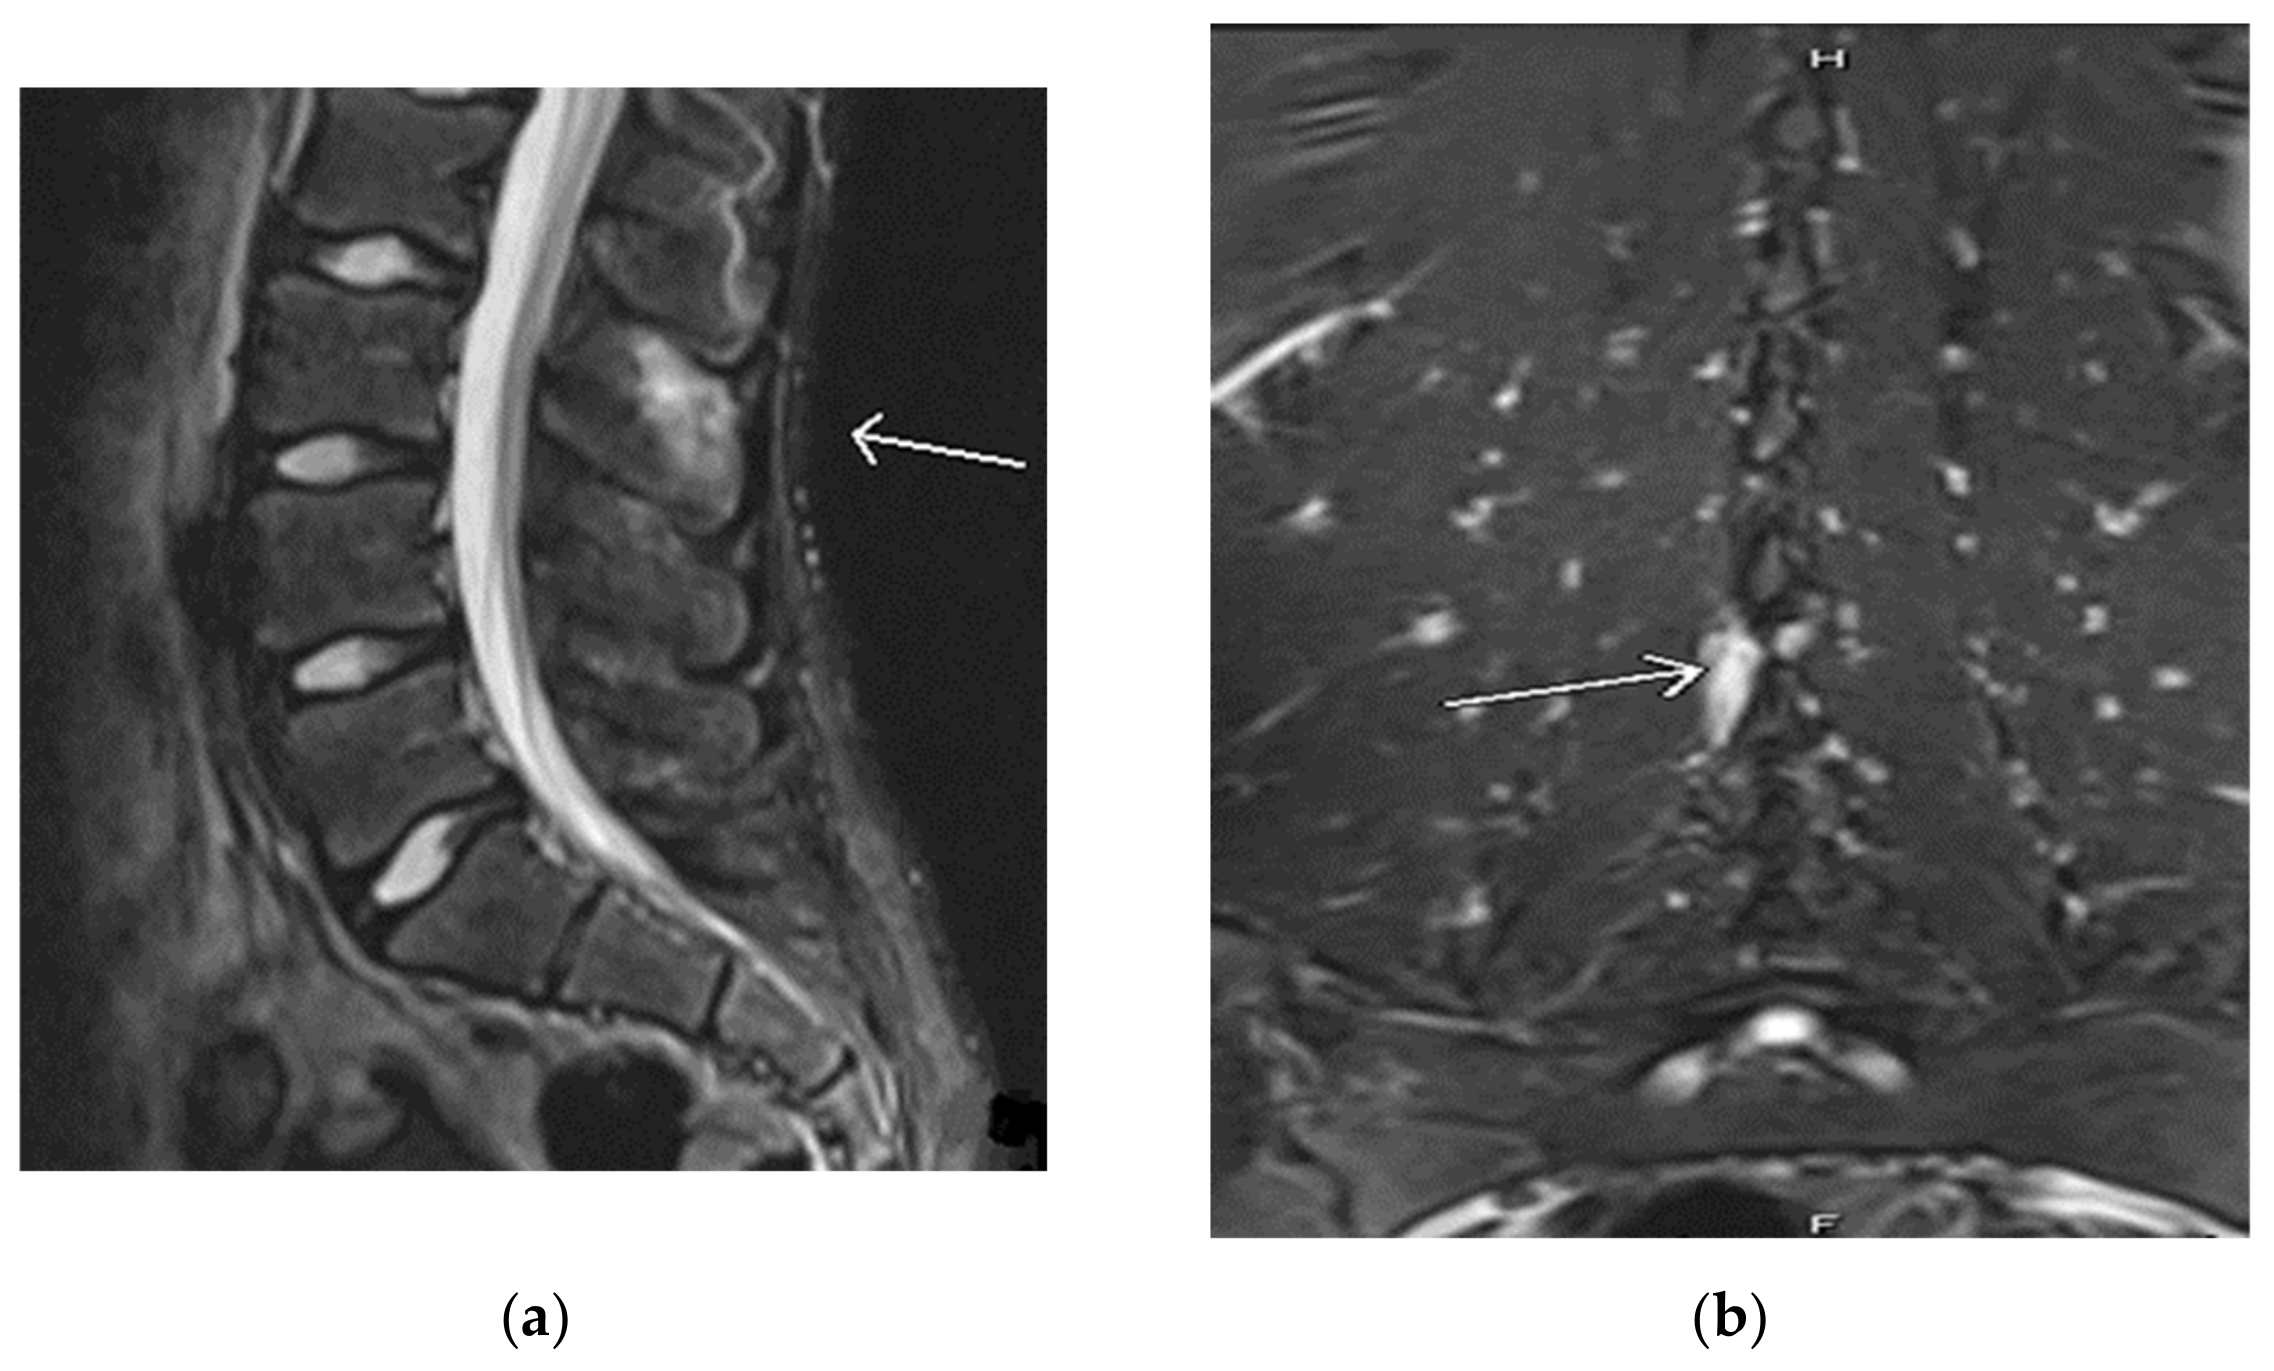

Our first case is of a 16-year-old active gymnast diagnosed with Baastrup’s disease in 2016 at the age of 11. She initially presented in 2014 with complaints of a sore back that worsened with extension and arching. Upon physical examination, there was pain to palpation along her thoracic spinous processes and adjacent thoracic paraspinal muscles. Upon neurological examination, the patient had no focal neurological deficits and negative provocative exam maneuvers (Spurling’s). The first thoracic magnetic resonance imaging (MRI) in February 2014 appeared normal; however, a repeat thoracic MRI in September 2014 showed early suspicion for spinous process abnormality at the thoracolumbar junction region vertebra, particularly T12 (see Figure 1).

Figure 1. (a) Magnetic resonance imaging (MRI) thoracic spine sagittal view shows an arrow pointing to signal abnormality at the tips of the spinous processes in the thoracolumbar junction region, particularly at T12. (b) MRI lumbar spine axial view shows an arrow pointing at mild hyperintensity in the T12 spinous process.